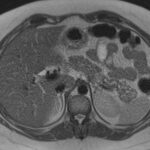

Mujer de 36 años que ingresa a Hospital Sanatorio Franchin el 11 de octubre de 2023 de forma programada para realización de duodeno pancreatectomía cefálica por tumor de cabeza de páncreas en estudio. Refiere hallazgo de lesión en forma incidental durante estudio de control hace dos meses por presentar antecedentes familiares (neoplasia endocrina múltiple). Se interna para manejo quirúrgico. Estudios de tomografía revelan formación nodular localizada en cabeza y cuerpo pancreático de paredes gruesas que mide 24 x 28 mm, que en resonancia se muestra hiperintensa en T2 y realce periférico luego de la administración de contraste endovenoso. Presenta restricción en la difusión con caída de la señal ADC, por lo que se vincula con una lesión de alta celularidad.